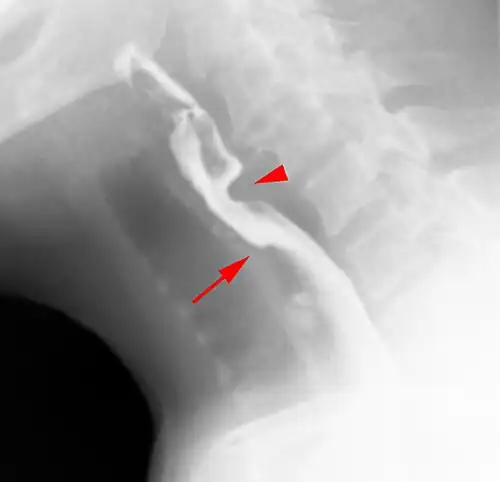

Esophageal webs are thin 2–3 mm (0.08–0.12 in) membranes of normal esophageal tissue consisting of mucosa and submucosa that can partially protrude/obstruct the esophagus. They can be congenital or acquired. Congenital webs commonly appear in the middle and inferior third of the esophagus, and they are more likely to be circumferential with a central or eccentric orifice. Acquired webs are much more common than congenital webs and typically appear in the cervical area (postcricoid).

The diagnostic test of choice is a barium swallow.